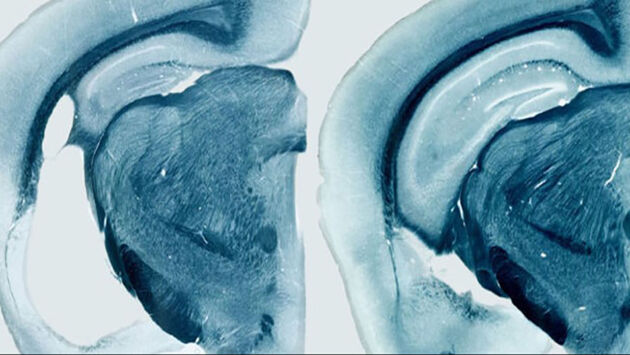

МОСКВА, 28 сен – РИА Новости. Биоматематики из Института системной биологии в Москве и их зарубежные коллеги разработали оптимальную стратегию борьбы с болезнью Альцгеймера, вычислив идеальное время начала и минимальные сроки лечения, и опубликовали ее в журнале CPT: Pharmacometrics & Systems Pharmacology. "Мы не делаем громких заявлений о том, что поняли причину болезни Альцгеймера. Мы показали, что наша модель помогает быстро и качественно оценить гипотезы. Самый главный вопрос, на который мы хотели ответить: как помочь пациенту? Мы смогли определить оптимальную схему лечения, но действительно ли это улучшит жизнь пациента — пока не понятно. Это требует реальных клинических испытаний" — рассказывает Татьяна Карелина из Института системной биологии в Москве. Запутанный клубок воспоминаний И болезнь Альцейгмера, и болезнь Паркинсона вызываются накоплением в нервных клетках различного белкового "мусора", который постепенно убивает нейроны в разных частях мозга. Их смерть ведет к потере памяти и старческому слабоумию в первом случае и к потере контроля над конечностями во втором. Ученые пока не понимают механизмов, заставляющих клетки мозга накапливать в себе тау-белок, бляшки бета-амилоида, клубки альфа-синуклеина, и прочих потенциальных причин развития этих болезней. Поэтому биологи не только не могут создать лекарства от болезней Альцгеймера и Паркинсона, но и понять, по каким причинам они развиваются. Российские ученые предлагают решить эту проблему математическим путем, не прибегая к длительным и дорогим экспериментам. Математики из Института системной биологии недавно сделали первый шаг в этом направлении, создав компьютерную модель того, как формируются бляшки бета-амилоида. Она может значительно ускорить поиск лекарства болезни Альцгеймера, так как подобные расчеты позволяют предсказать эффективность действия различных веществ на скопления белка, не проводя реальные эксперименты в лаборатории. Данная модель уже помогла ученым раскрыть причины того, почему некоторые перспективные лекарства от болезни Альцгеймера провалились в клинических испытаниях, однако она не описывала то, как именно развивается болезнь. Формула здоровья Российские ученые и их зарубежные коллеги решили эту проблему – они проанализировали результаты нескольких десятков клинических исследований, посвященных тому, как растут амилоидные бляшки в мозге человека и животных, и "перевели" их выводы на язык математики, понятный для компьютера. Плодом всех этих усилий стал набор формул с 30 переменными, при помощи которых Карелиной и ее коллегам удалось выявить несколько ключевых факторов в развитии болезни и понять, каким образом и как долго ее следует лечить. В частности, оказалось, что основной причиной развития болезни Альцгеймера является то, что клетки мозга теряют способность самостоятельно разлагать нерастворимые скопления бета-амилоида, что и приводит к образованию бляшек и массовой гибели нейронов. Дальнейшие расчеты показали, что все существующие и будущие лекарства, уничтожающие бляшки бета-амилоида, могут оказать серьезный эффект на мозг пациента только в том случае, если лечение будет начато как можно раньше, не позже чем в 60 лет, и оно должно продолжаться как минимум год. Сейчас российские математики готовят свою модель для презентации на Американской конференции по фармакометрике – важнейшем ежегодном мероприятии для разработчиков новых препаратов. Ученые надеются не только обсудить свои результаты с сообществом, но и найти новых партнеров для дальнейшей работы.